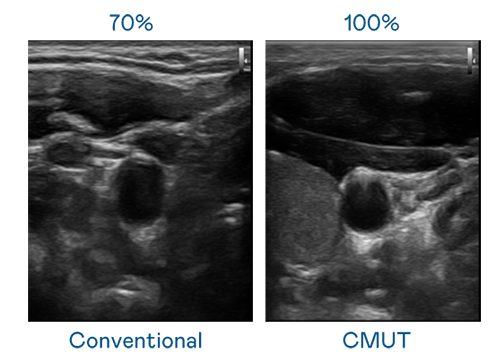

CMUT 技術是一種用電容式微機電元件來產生超音波訊號的技術。與傳統 PZT 壓電式技術相比,CMUT 頻寬增加 30%,更寬頻的超音波訊號讓影像解析度大幅提升,是實現高影像品質醫療超音波掃描、促進精準醫療發展的關鍵技術。

大頻寬帶來超清晰影像

超音波影像的解析度高低,首先取決於探頭能發出的訊號頻寬。人生就是搏 CMUT 可提供高清晰的超音波訊號,提供高頻寬、高靈敏度、影像紋理細節更高的超音波影像,協助醫護人員縮短影像判讀時間及利用精準的醫療影像進行診斷。